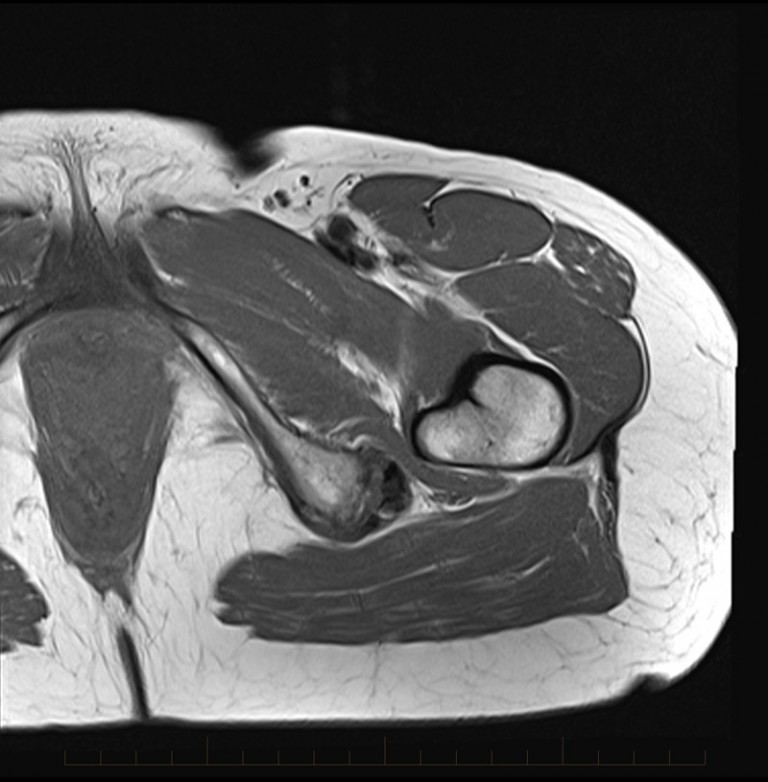

Typical MRI findings of bilateral ischial bursitis bilateral Weaver’s Hamstring Bursitis Ischiogluteal bursitis is inflammation of the bursa which lies between the hamstring tendon and the bone. The hamstring muscles are responsible for bending the knee and straightening the hip during activity and are particularly active during running, jumping and kicking. The ischiogluteal bursa works to allow the gluteal and hamstring muscles to slide smoothly and without friction over the nearby. Hamstring Bursitis.

From www.mri.melbourne

MRI Hamstring bursitis MRI at Melbourne Radiology Clinic Hamstring Bursitis Diagnosis can be confirmed with. The ischiogluteal bursa works to allow the gluteal and hamstring muscles to slide smoothly and without friction over the nearby bone (ischial tuberosity). Ischial bursitis happens when the bursae that cushion your hip bones become painful and inflamed due to irritation. Diagnosis can be made clinically with ecchymosis in the posterior thigh, tenderness over the. Hamstring Bursitis.

From symmetryptmiami.com

mrihamstringbursitis1 MRI at Melbourne Radiology Clinic Hamstring Bursitis The ischiogluteal bursa works to allow the gluteal and hamstring muscles to slide smoothly and without friction over the nearby bone (ischial tuberosity). Hamstring tendinitis is an overuse injury that affects the hamstring tendons where they attach to the ischial tuberosity. Ischial bursitis happens when the bursae that cushion your hip bones become painful and inflamed due to irritation. The. Hamstring Bursitis.